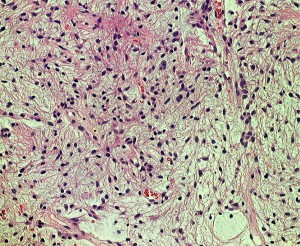

幼児の毛様細胞性星細胞腫

血管に富み,増大傾向が著しかった例です。MIB-1(右下)が20%以上あり異常に高値でした。